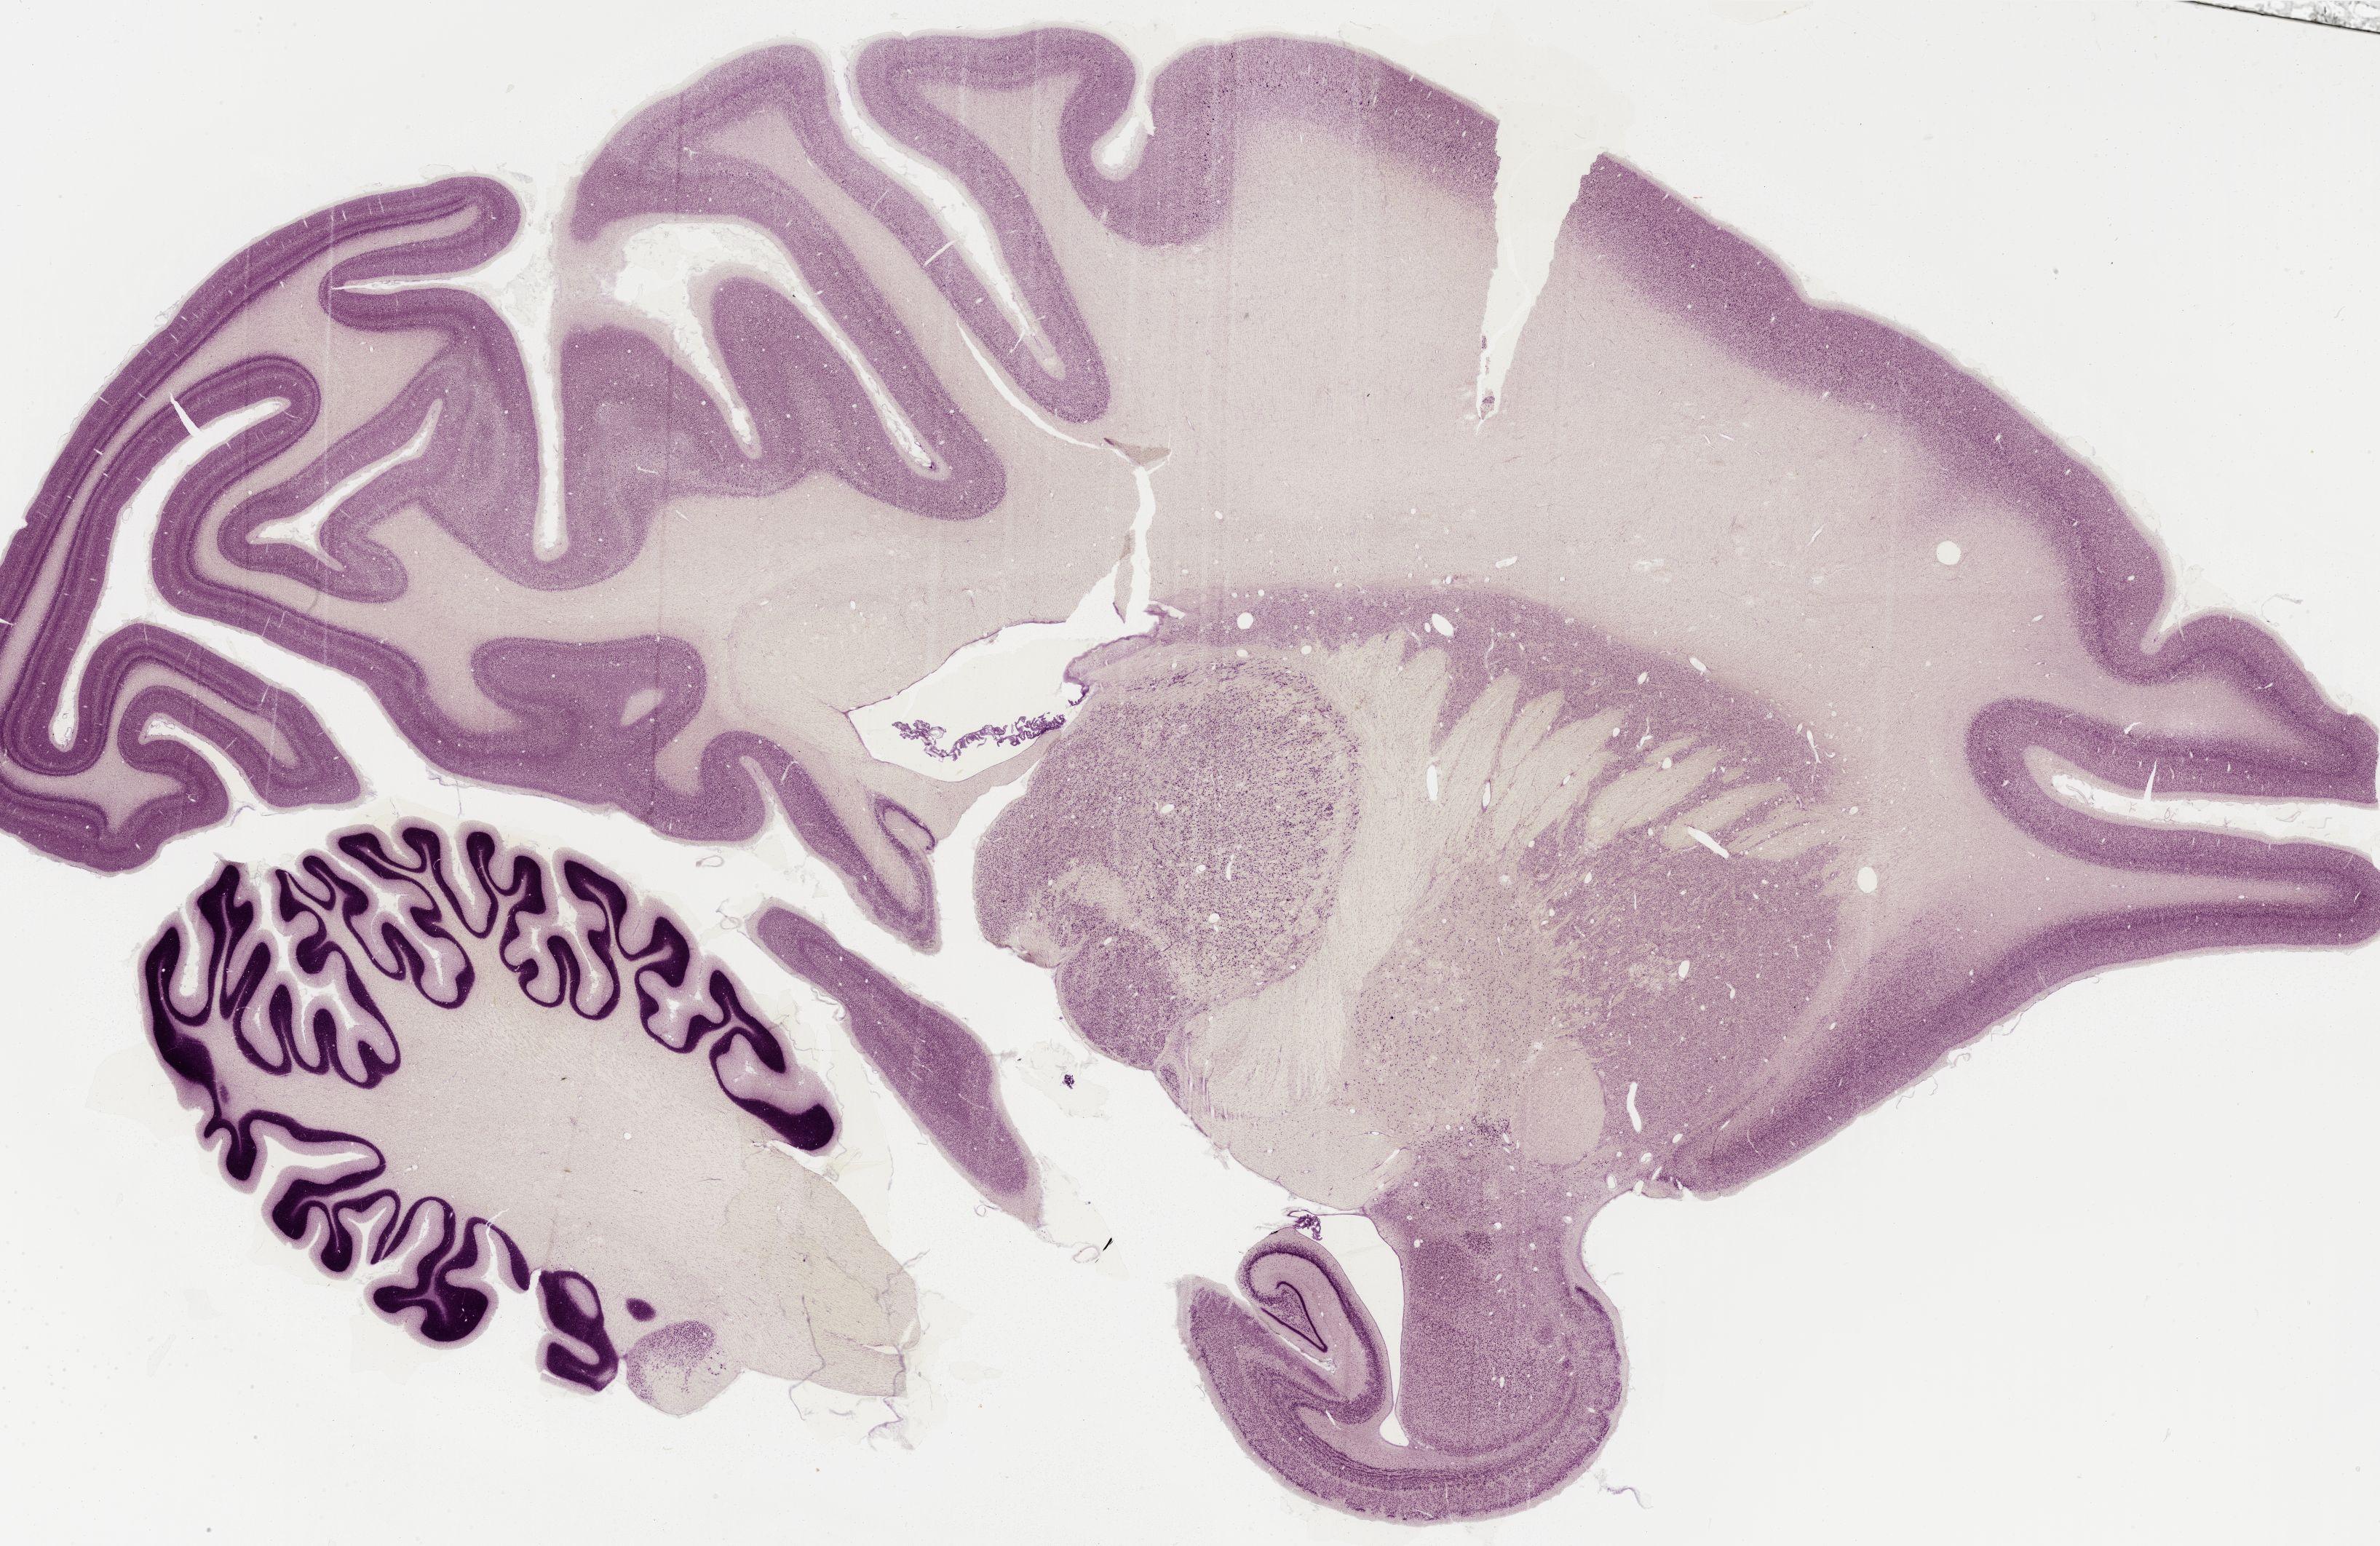

Datasets -> Macaca Mulatta -> Nissl, sagittal, histo, Whole-Brain, adult

[ Metadata ]   ·   Source: Edward G. Jones

Displaying Sections 161 thru 200 of 295 Sections for this Dataset

0365 - labeled